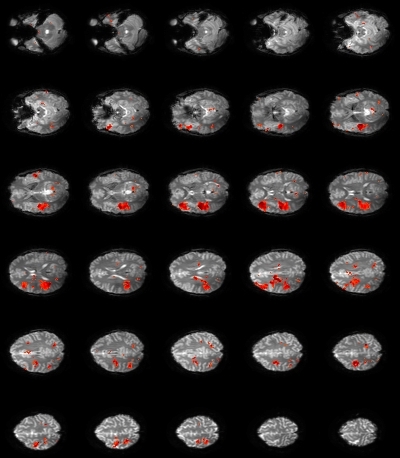

Rationale: Epilepsy diagnosis and treatment benefit from the mapping of interictal epileptiform discharges (IED), which is achieved at much higher spatial resolution with functional MRI than with scalp EEG. In previous studies that use either simultaneous EEG-fMRI (Pittau et al., Neurology 78:1479) or fMRI alone (Khatamian et al., Epilepsy Res 94:177), fMRI signal analysis is based on amplitude increases in each voxel, which represent increased neural activities during IED. However, IED are also accompanied by increased neural synchronization across a local area (e.g. 6-20 cm2) surrounding the IED (Wennberg et al., Clin Neurophys 122:1295). This encouraged us to develop new fMRI analysis paradigms based on the increase in synchronization of fMRI signals across voxels within a local area during IED. Such synchronization can be measure by local degree centrality (LDC), a network metric of local functional connectivity (Sepulcre et al., PLoS Comp Biol 6:e1000808).Methods: One-hour simultaneous scalp EEG (32 channels) and whole-brain fMRI (resolution: 3 mm, 2.5 s) data were acquired from 5 patients with focal epilepsy, and pre-processed using steps similar to that in previous studies. For IED mapping that uses EEG, fMRI data of 20 s duration around each IED event identified from EEG were stitched together into an IED-containing time segment, and IED-absent time segments of the same duration were constructed for comparison. LDC was computed for each time segment and each voxel as the sum of the fMRI signal correlation coefficients between this voxel and all voxels within 1.4 cm distance (i.e. an area of > 6 cm2). The statistical significance (z-score) of LDC difference between IED-containing and IED-absent time segments was mapped. For IED mapping without EEG, LDC was computed for segments of 40 s duration slid across time, effectively creating a time series of LDC values for each voxel. Using cluster analysis (Khatamian et al.), voxel clusters that have the maximum LDC value at the same time were isolated and then inspected visually to identify the cluster most likely associated with IED.Results: For mapping that utilizes EEG, focal regions with significant LDC increases during IED were identified in all 5 patients, and their locations were concordant with EEG. Figure 1 shows the LDC z-score map in a patient with EEG spikes in left temporal lobe. The LDC-based approach performed better than the conventional EEG-fMRI method, which failed to identify concordant activation regions in 2 of the 5 patients who had relatively fewer events. For mapping without EEG, the LDC-based approach identified concordant voxel clusters in 3 patients, again with better performance than the conventional method. The resultant map (Figure 2) is often less specific than when using EEG and involves resting-state networks unrelated to IED, consistent with previous studies.Conclusions: The new method based on local fMRI signal synchronization is at least as effective in mapping interictal activities as the conventional methods based on signal amplitude, both when using simultaneous EEG to identify IED events and when without EEG.